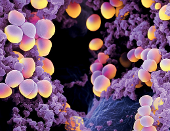

₦48,000.00Infections For Men- Gonorrhea, Staphylococcus, Syphilis, or any other pathogenic bacterial.

₦48,000.00Infections For Women- Gonorrhea, Staphylococcus, Pelvic Inflammatory Disease, Candidiasis, syphilis, Vaginal Discharge